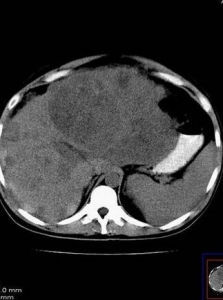

3.超聲及CT檢查

不僅可顯示少量的腹腔積液、還可顯示肝臟的大小、肝臟包膜的光滑度,肝內占位性病變。心臟的大小、結構、心臟流入道及流出道的情況、血流情況。腎臟的大小、形態、結構等。

腹腔積液的診斷一般較容易,除影像學檢查外,主要依據腹部叩診法:腹腔積液達500ml時,可用肘膝位叩診法證實;1000ml以上的腹腔積液可引起移動性濁音,大量腹腔積液時兩側脅腹膨出如蛙腹,檢查可有液波震顫;小量腹腔積液可借超聲和腹腔穿刺檢出,超聲示肝腎交界部位有暗區。CT的靈敏度不如超聲。